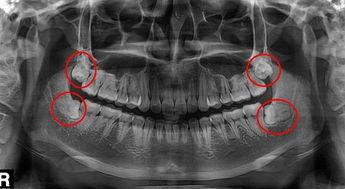

智齒發炎的時候,智齒周圍的組織是腫脹的,會(hui) 有嚴(yan) 重疼痛和不適,如果輕易拔牙後,炎症會(hui) 更嚴(yan) 重,還會(hui) 造成拔牙創口感染。所以一般有炎症,發生疼痛的時候到醫院要求拔牙是不能進行的,而是需要先到醫院做局部衝(chong) 洗再結合一些消炎止痛藥物服用後,等到炎症消除了,再到醫院進行拔牙。

一般來說,智齒不疼了,恢複正常了,就能到醫院拔牙了。至於(yu) 要多長時間,這個(ge) 和每個(ge) 人的恢複情況有關(guan) 係,不過一周左右應該差不多了。不過還需要滿足拔牙適應症,比如說月經期、孕期等特殊時期不建議拔牙,因為(wei) 拔牙是一個(ge) 小型的外科手術,所以別小看了,如果醫生技術不好,護理不好,容易出現幹槽症,也就是拔牙後久久不愈合的情況,因此,需要多多注意。